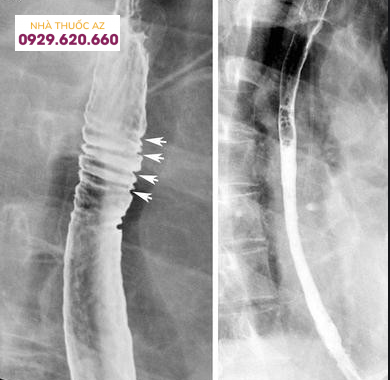

Hình 5. Hình ảnh các vòng thực quản trên chụp Baryt, tương ứng với các vòng tròn đồng tâm của thực quản được nhìn thấy trên nội soi

Hình 6: Hình ảnh các vòng thực quản trên chụp Baryt ở một bệnh nhân bị viêm thực quản bạch cầu ái toan (Nguồn: abdominalkey.com)

Đường kính của đoạn hẹp trung bình khoảng 1cm và vị trí hẹp ở phía đoạn thực quản trên/giữa có xu hướng dài hơn so với đoạn dưới. Tùy vị trí đoạn hẹp trên chụp Baryt vẫn cần cân nhắc đến các chẩn đoán phân biệt khác. Các nguyên nhân khác gây hẹp ở đoạn thực quản trên hoặc giữa bao gồm thực quản Barrett, xạ trị vùng trung thất, sử dụng một số loại thuốc như NSAID, quinidine, trong khi hẹp ở đoạn dưới thực quản có thể do viêmthực quản trào ngược. Cần chú ý những bệnh nhân có hình ảnh hẹp thực quản trên chụp Baryt thường có triệu chứng nuốt khó và đây chỉ là một dấu hiệu gợi ý, cần kết hợp nhiều yếu tố liên quan đến bệnh sử, triệu chứng lâm sàng, hình ảnh nội soi và mô bệnh học.Vòng thực quản cũng là hình ảnh hay gặp với nhiều thuật ngữ được sử dụng như “khí quản hóa thực quản” hay “thực quản dạng vòng”. Vị trí và sự phân bố của các vòng thực quản rất khác nhau trên nội soi, có thể ở các đoạn của thực quản hoặc phân bổ lan tỏa nhiều chỗ. Đôi khi những vòng này có thể gây hẹp khiến dây sợi khó đưa qua được. Trên chụp Baryt, các vòng này thường nhiều, hay xuất hiện gần nhau, có dạng đồng tâm dọc theo lòng thực quản.